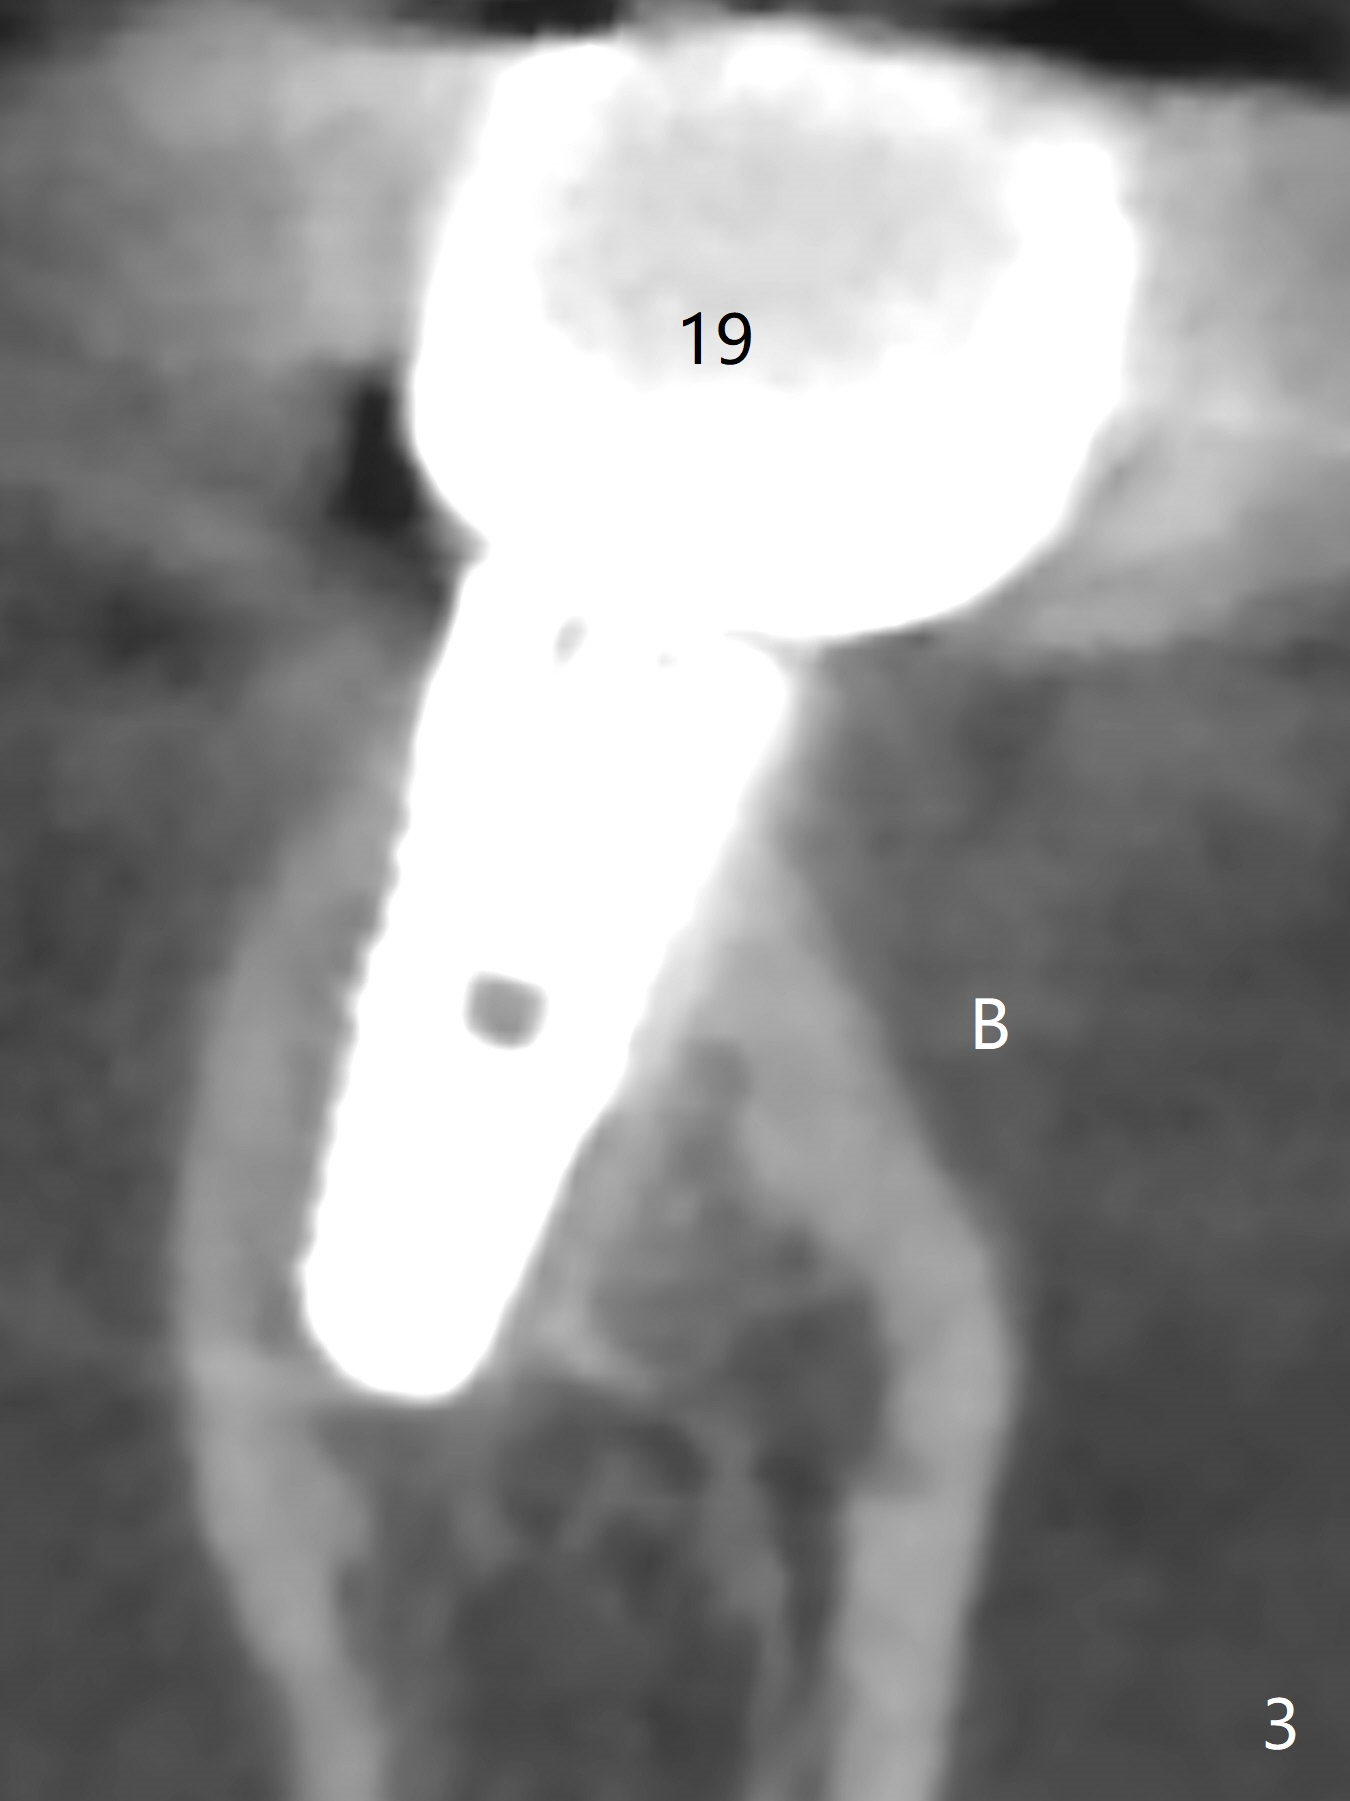

Twenty six months post cementation, periimplantitis develops buccally at #30 (Fig.1) due to buccal (B) placement (Fig.2) with buccal thread exposure (red line), as compared to the same sized implant at #19 (Fig.3). After removal of the crown and abutment and incision, use Titanium brush to clean the exposed threads. Following implant removal and removal of the lingual bone, place the same implant lingually (Fig.4 arrow) with the used-to-be-exposed surface facing lingual (Fig.4 red line). The buccal gap will be filled with autogenous bone harvested lingually and allograft. Use 2-3 pieces of PRF membranes to close the wound, i.e., to bury the implant. A 5x13 mm implant (Fig.5) placed lingually (Fig.6 L) appears to be unable to gain more than .77 mm native bone (Fig.7). Lab declines to make a guide.